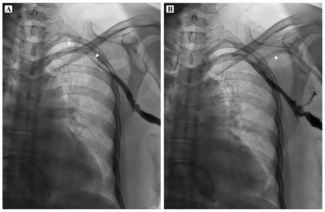

A woman in her 60s presented with symptomatic complete heart block and was advised permanent pacemaker implantation. During the procedure, left axillary vein access was attempted using fluoroscopic landmarks but was not successful. A venogram...